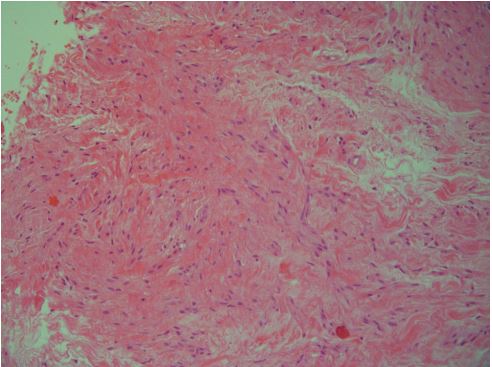

A 45-year-old Caucasian female attended our outpatient clinic during her annual follow-up, with a painless, palpable mass in the upper outer quadrant of her left breast. She denied family history with breast or gynecological malignancies and had never received hormonal therapy or other medication. A clinical examination revealed a painless palpable mobile lump in the aforementioned area at a distance of approximately 10 cm from the nipple. There was no axillary or supraclavicular lymphadenopathy. The other breast was into normal appearance and consistency. The lesion had incidentally been found two years previous to this during her annual mammogram and was originally considered to be fibroadenoma. That ultrasound had detected a hypoechoic oval shape nodule, with no detectable Doppler flow, located in the upper outer quadrant of the left breast, measuring 2.6 cm (Figure 1). The follow-up mammogram detected an enlarged, dense, well-circumscribed oval lesion with no calcifications inside or around, without lymphadenopathy (Figure 2). The lump was classified as category 4 according to BIRADS (Breast ImagingReporting and Data System) criteria. Based on clinical and imaging findings, a Tru Cut biopsy through U/S was then conducted. The resulting pathology revealed spindle cells with elongated cigar-shaped nuclei and eosinophilic cytoplasm (H+E stain x 20) (Figure 3). Despite the benign nature of the tumor, the patient was offered the option of surgical removal of the lump in order to avoid diagnostic dilemmas and pitfalls. A consent form was signed and under general anesthesia the lesion was resected in macroscopic clear margins leaving a drain in place. Postoperative course was without noteworthy incidence and the patient was discharged the hospital the next day. The pathology of the specimen showed intersecting fascicles of elongated smooth muscle cells with no atypia or mitotic activity. Immunohistochemistry depicted strong expression of desmin, a characteristic of smooth muscle neoplasms, which confirmed the diagnosis of leiomyoma, while the absence of p63 marker excluded metaplastic carcinoma (Figures 4,5). Two years after the operation the patient has no symptoms and the mammogram shows no evidence of recurrence.

Figure 3: Higher magnification of the lesion showing spindle cells with elongated cigar-shaped nuclei and eosinophilic cytoplasm. (H+E stain x 20).